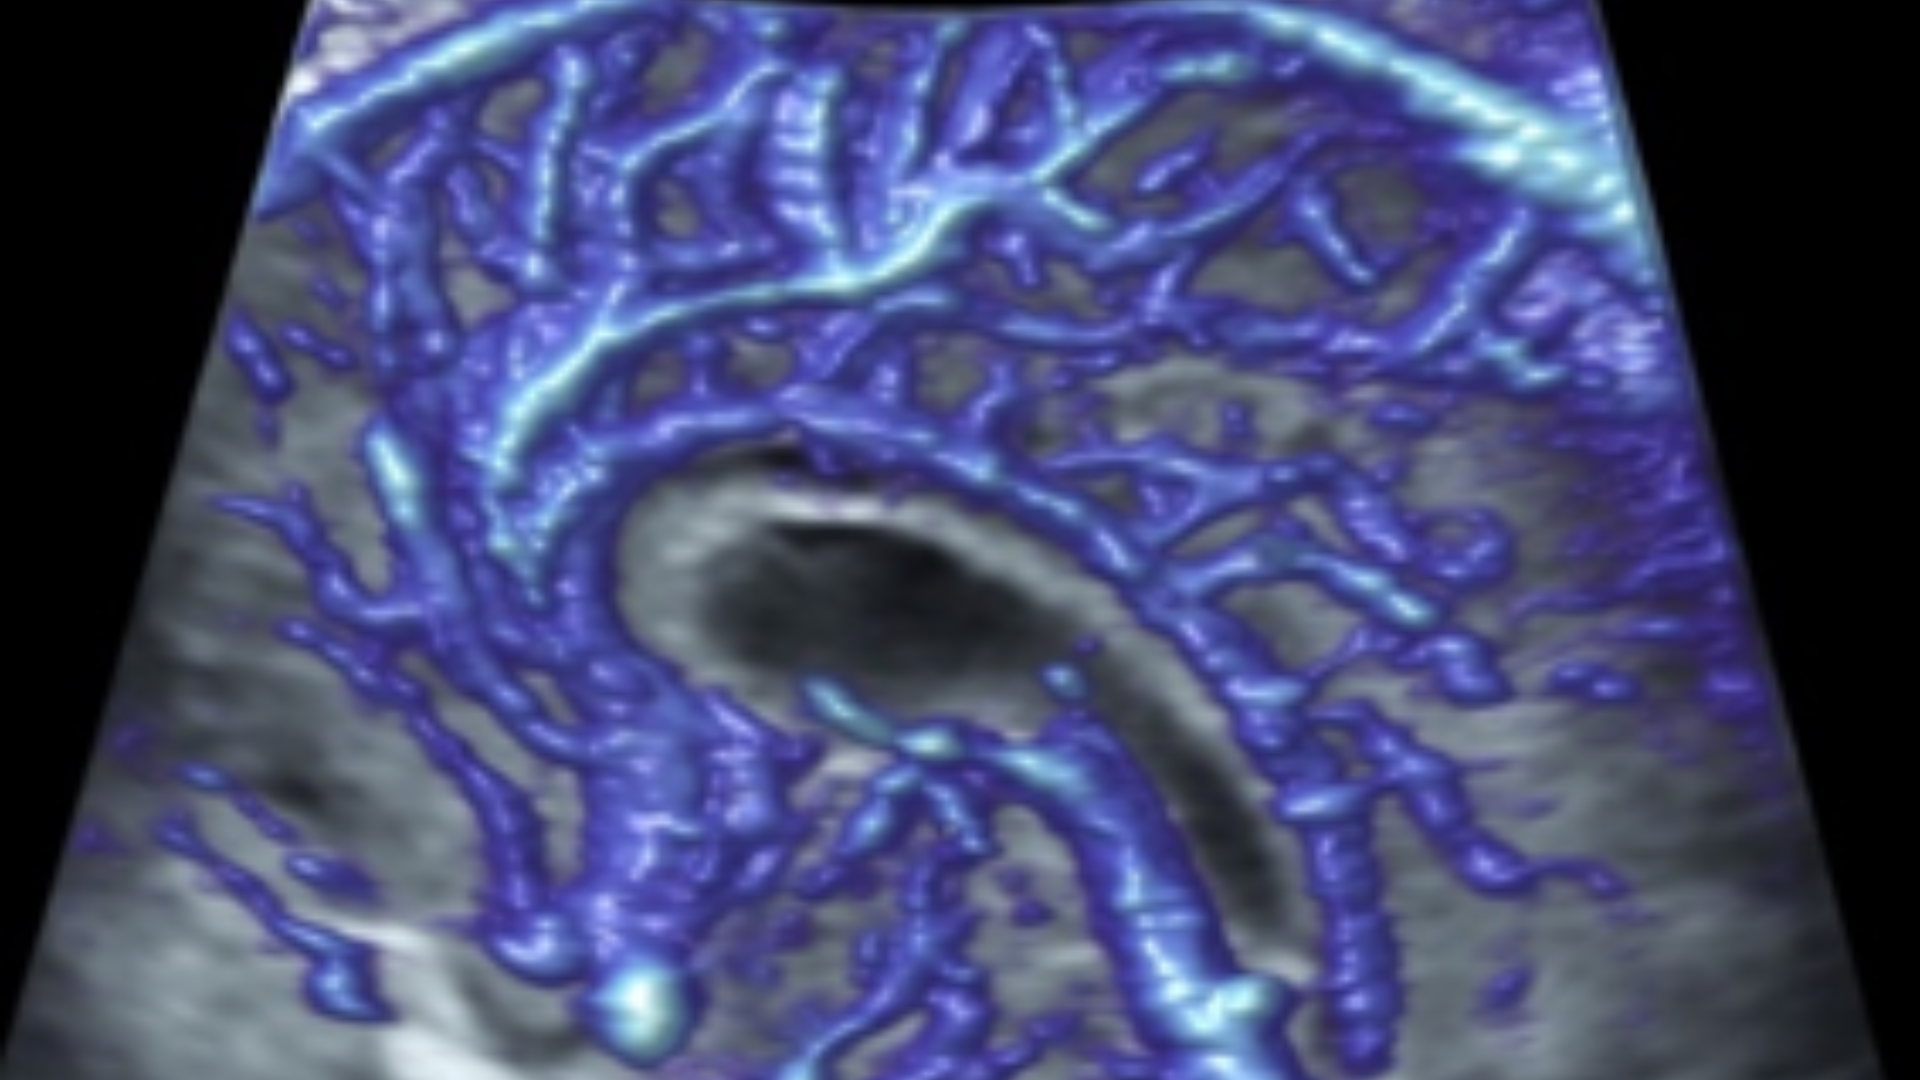

L’Université Paris Cité franchit une nouvelle étape dans le domaine de l’imagerie médicale anténatale avec l’acquisition d’un système d’Imagerie par Résonance Magnétique (IRM) 1,5T ARTIST™ de GE HealthCare. Cet équipement de pointe renforce les capacités de la Plateforme LUMIERE à l’hôpital Necker-Enfants malades, plateforme intégrée de soins, de recherche clinique et d’enseignement en imagerie médicale de la femme enceinte, du fœtus et du placenta.

L’acquisition de cette nouvelle IRM s’inscrit dans le cadre du protocole de recherche « LUMIERE SUR LE FETUS », dont les objectifs sont d’améliorer la prise en charge des pathologies anténatales, d’affiner leur pronostic et de contribuer à la réduction de la morbidité et de la mortalité à court, moyen et long terme. Cette acquisition a été rendue possible grâce au don exceptionnel de la Fondation LUMIERE d’un montant de 250k euros ainsi qu’au soutien de l’Université Paris Cité à hauteur de 670k euros.

Depuis 2020, la Plateforme LUMIERE offre aux femmes enceintes volontaires, entre 16 et 36 semaines d’aménorrhée et suivies à l’hôpital Necker-Enfants malades, la possibilité de participer activement à l’avancée de la recherche en médecine fœtale, tout en bénéficiant d’une IRM fœtale au cours de leur grossesse, réalisée dans un cadre sécurisé et encadré.